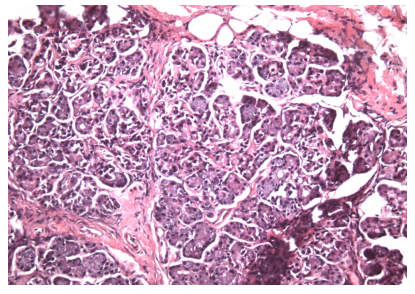

图 5 异位泪腺组织的病理图片(HE 染色,X40)

Figure 5 Pathological images of ectopic lacrimal gland tissue (HE staining, X40)